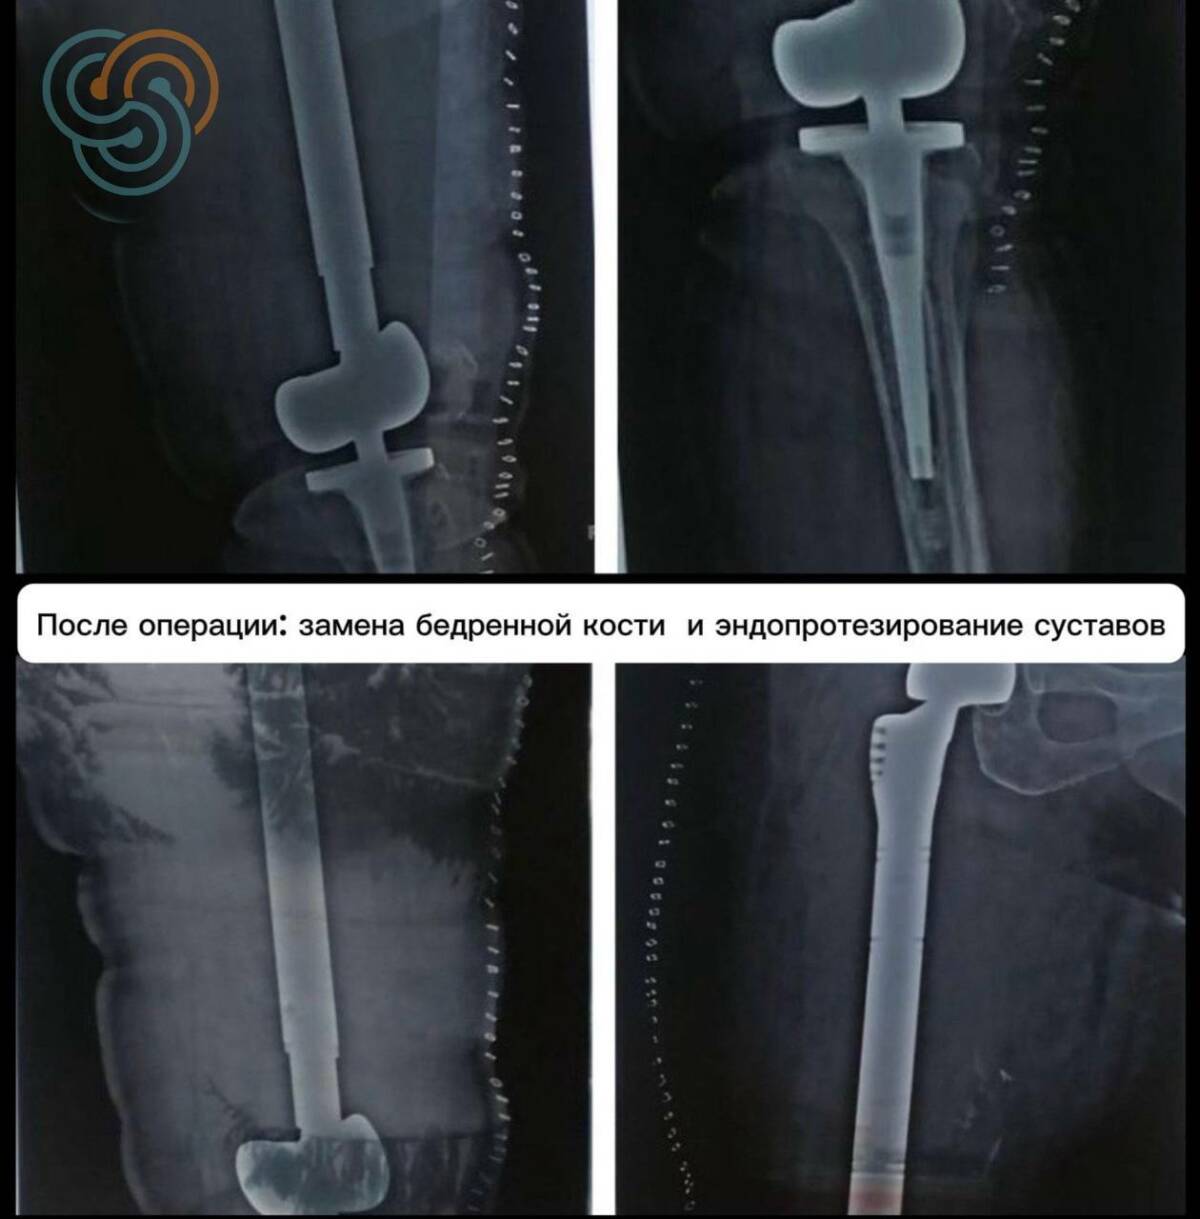

В декабре была выполнена операция, которая ранее не проводилась в Татарстане: полная замена пораженной бедренной кости с тотальным эндопротезированием тазобедренного и коленного суставов.

«Объем поражения был крайне большим – фактически затронута вся бедренная кость. Здесь нам удалось выполнить радикальное хирургическое вмешательство с сохранением конечности», – отметил заведующий онкологическим отделением № 16 Ильдар Сафин.

На фоне химиотерапии удалось добиться больших результатов: значительно уменьшился болевой синдром, появилась возможность вставать и ходить с ортезом. К работе подключились реабилитологи. Восстановление шло постепенно. Когда стало ясно, что опухолевый процесс удалось взять под контроль, врачи перешли к хирургическому этапу.